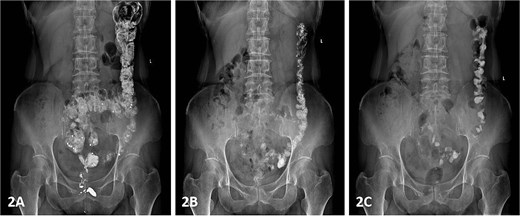

Colonic transit time assessment was performed using radiopaque markers. At 24 h post-ingestion, 19 markers were retained within the colon, with complete clearance observed at 48 and 72 h, confirming normal colonic motility (Fig. 2). Defecography demonstrated a Grade III RC, characterized by a maximal depth of 76 mm during straining and persistent barium retention post-evacuation, consistent with obstructed defecation syndrome (ODS) (Fig. 3).